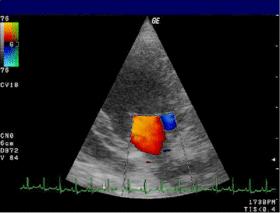

Doppler echocardiography is a procedure that uses Doppler ultrasonography to examine the heart.[1] An echocardiogram uses high frequency sound waves to create an image of the heart while the use of Doppler technology allows determination of the speed and direction of blood flow by utilizing the Doppler effect.

An echocardiogram can, within certain limits, produce accurate assessment of the direction of blood flow and the velocity of blood and cardiac tissue at any arbitrary point using the Doppler effect. One of the limitations is that the ultrasound beam should be as parallel to the blood flow as possible. Velocity measurements allow assessment of cardiac valve areas and function, any abnormal communications between the left and right side of the heart, any leaking of blood through the valves (valvular regurgitation), calculation of the cardiac output and calculation of E/A ratio[2] (a measure of diastolic dysfunction). Contrast-enhanced ultrasound-using gas-filled microbubble contrast media can be used to improve velocity or other flow-related medical measurements.

An advantage of Doppler echocardiography is that it can be used to measure blood flow within the heart without invasive procedures such as cardiac catheterization.